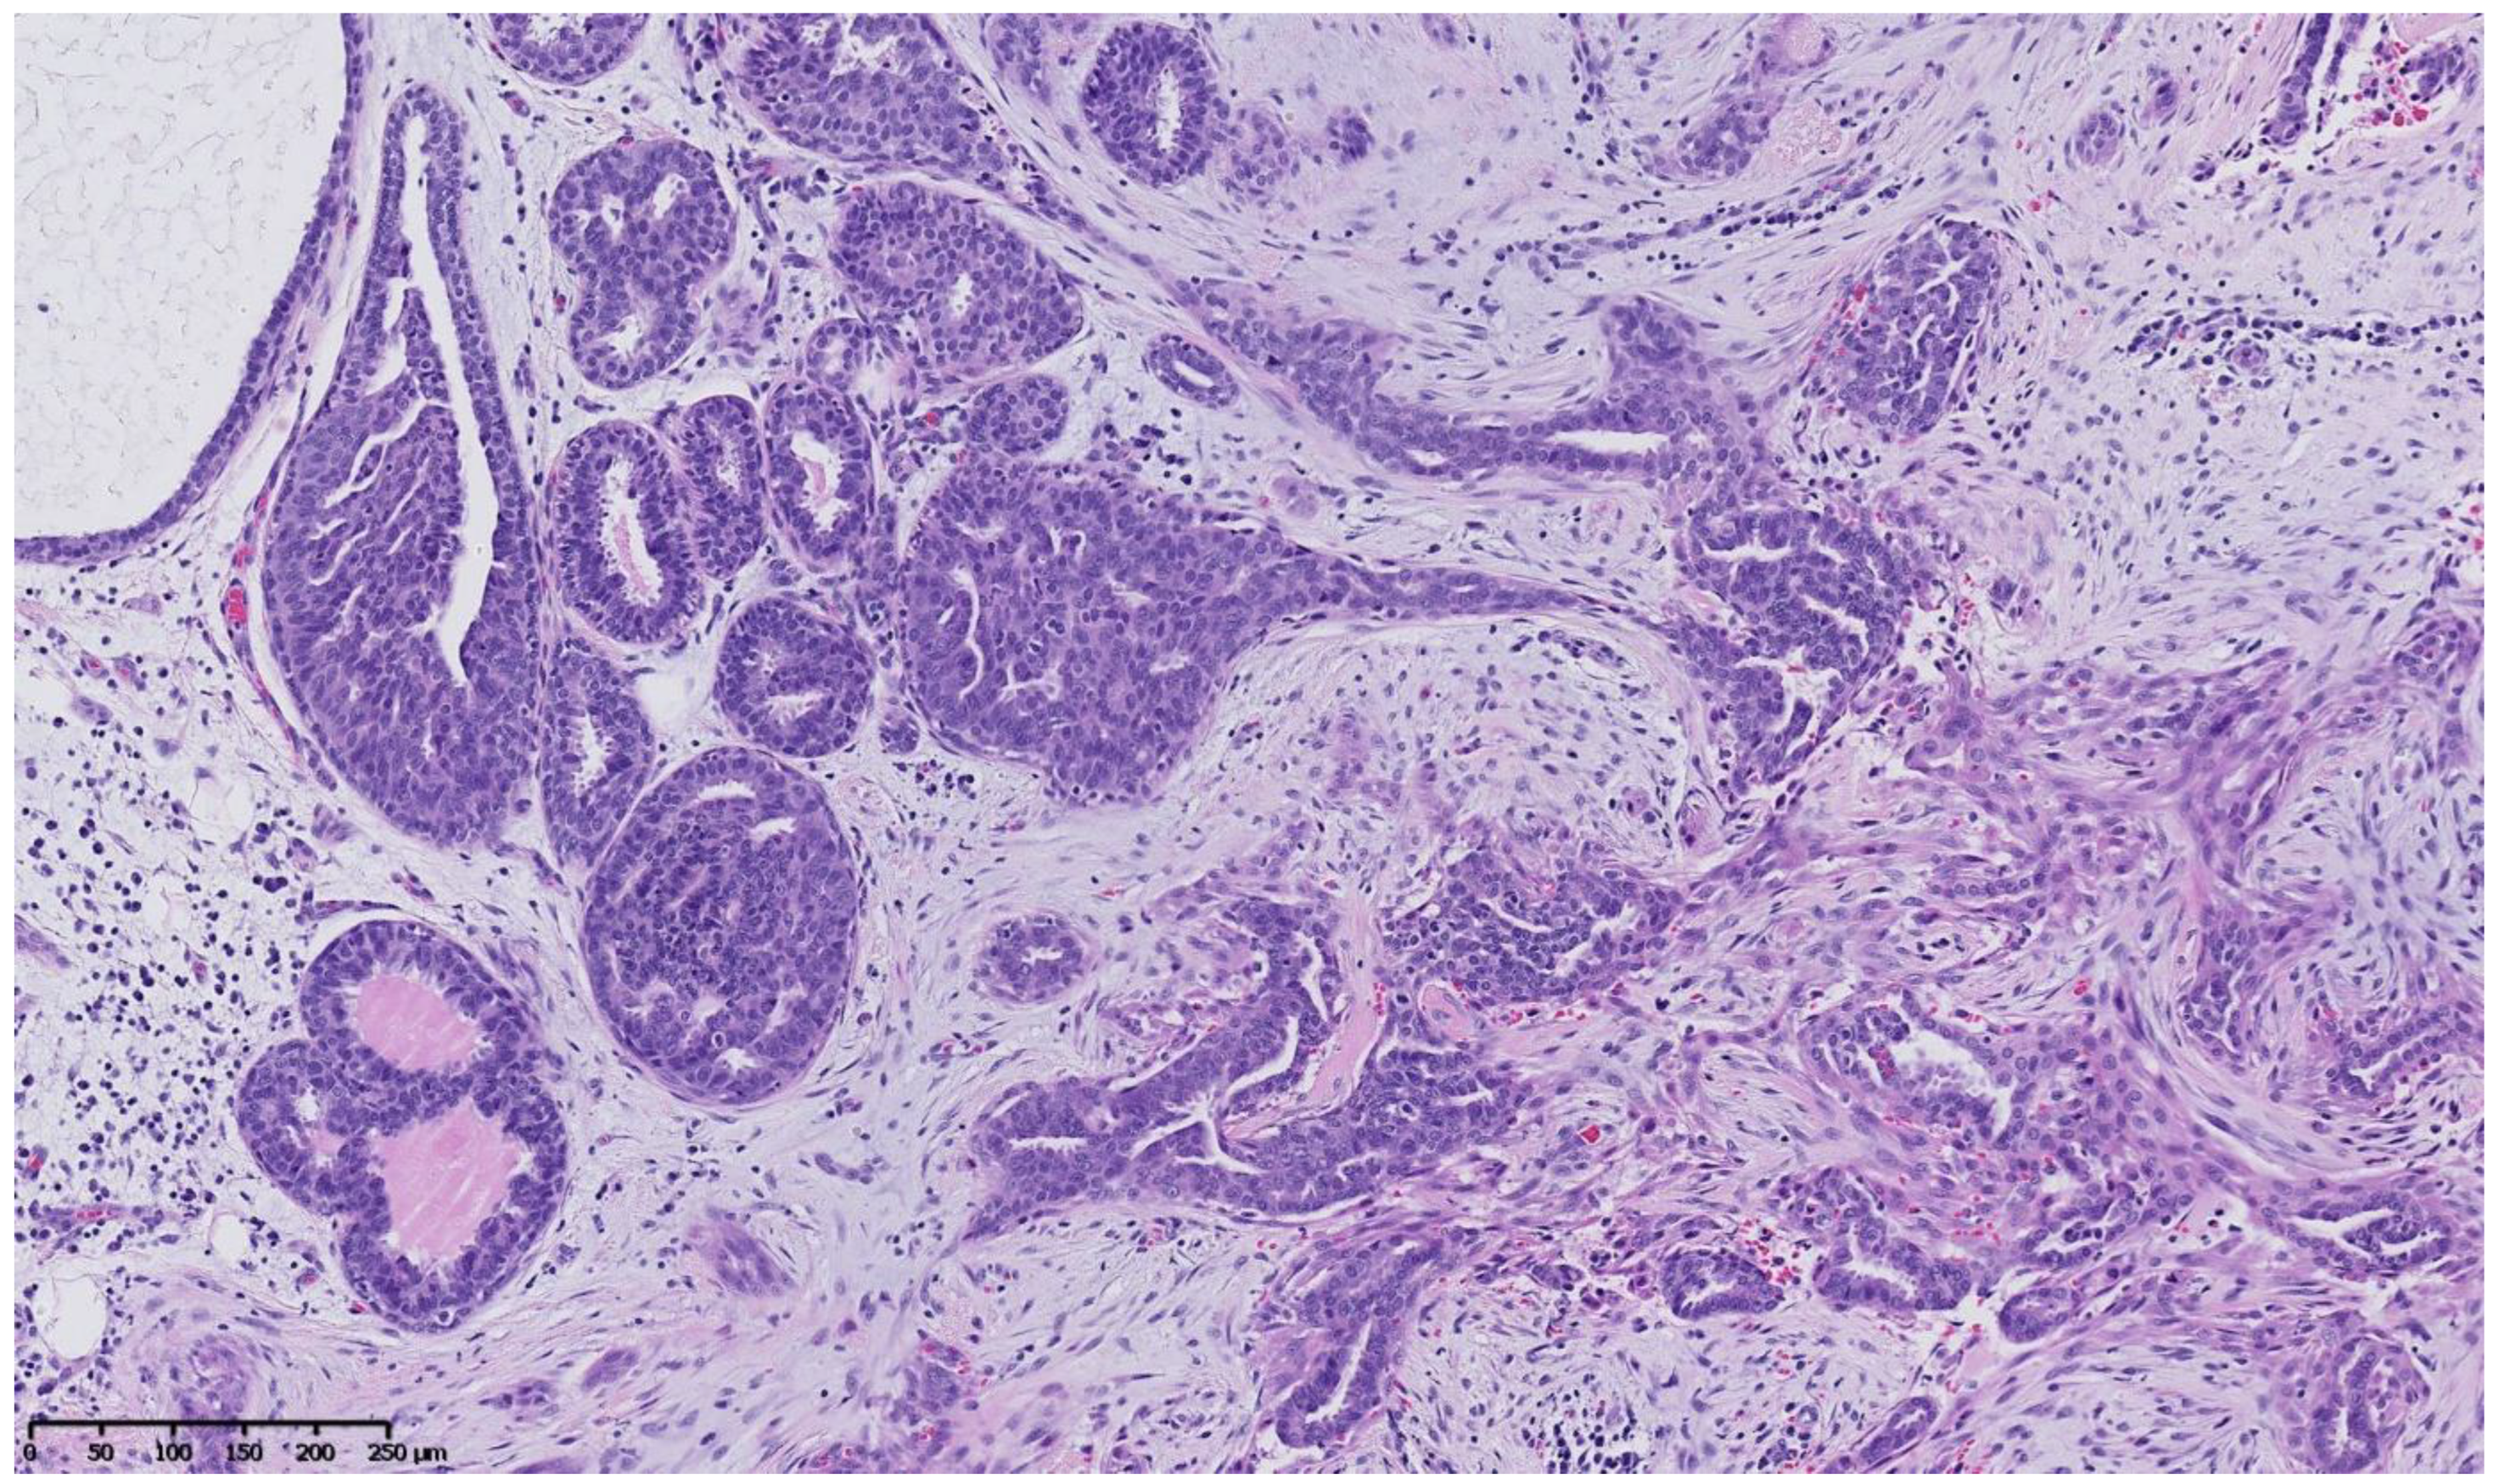

4. Benign Breast Lesions in Transwomen

5. Risk of Breast Cancer: What Do We Know?